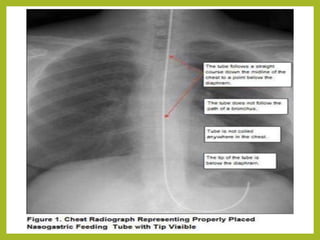

X-rayconfirmation

7. Emphasizetheneedtomouthbreatheandswallowduringtheprocedure 8. Swallowingfacilitatesthepassageofthetubethroughtheoropharynx. 9.Whenthetipofthetubereachesthecarniastopand listenfor airexchangefrom thedistalendofthetube.Ifairisheardremove thetube. 10. Advancetubeeachtime clientswallowsuntildesiredlengthhasbeenreached 11. Donotforcetube.Ifresistanceismet(cough,chokeor becomecyanotic)stop advancingthetubeandpullback 12. Checkplacementofthetube. X-rayconfirmation TestingpHofaspirate 13.Securethetubewithtapeor commercialdevice